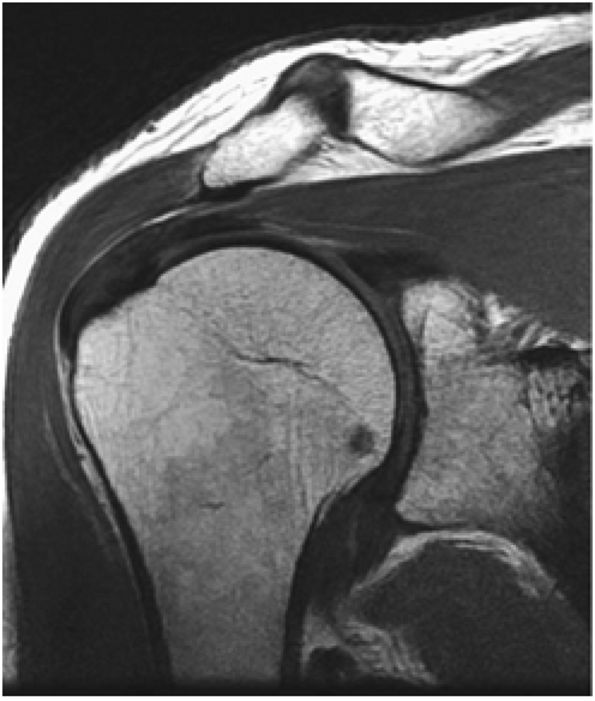

On anterior and midcoronal oblique images, the supraspinatus muscle and its central tendon are seen in continuity. The low-density supraspinatus tendon is defined at its insertion on the greater tuberosity. The subacromial bursa is interposed between the rotator cuff and the acromion. A fibrofatty layer lies between the acromion, the AC joint, and the superior bursal layer.

On midcoronal images, the muscle belly of the supraspinatus extends laterally beyond the glenoid before its central tendon reaches the musculotendinous junction of the rotator cuff. The axillary pouch of the IGHL, with its attachment to the anatomic neck of the humerus and the inferior pole of the glenoid, can also be seen on these images. It is not unusual to see variable

amounts of fluid in the axillary pouch in the presence of a joint effusion. Otherwise, the axillary pouch is collapsed. The presence of a glenohumeral joint effusion is associated with osteoarthritis and rotator cuff disease.42 The axillary pouch can be followed from anterior to posterior on coronal oblique images through the shoulder. -

On midcoronal to posterior coronal sections, there is a subtle transition between the supraspinatus and the conjoined insertion of the infraspinatus tendon. Posterior to the AC joint, the supraspinatus tendon forms a conjoined attachment to the greater tuberosity with the infraspinatus tendon. On more posterior sections, the infraspinatus tendon may be mistaken for the supraspinatus tendon, which may be out of the plane of section. Humeral head articular cartilage, intermediate in signal intensity on T1-weighted images, is interposed between the low-signal-intensity supraspinatus tendon superiorly and the cortex inferiorly. The posterior circumflex humeral artery and the axillary nerve are identified medial to the coracobrachialis, the latissimus dorsi, and the teres major muscles and tendons.